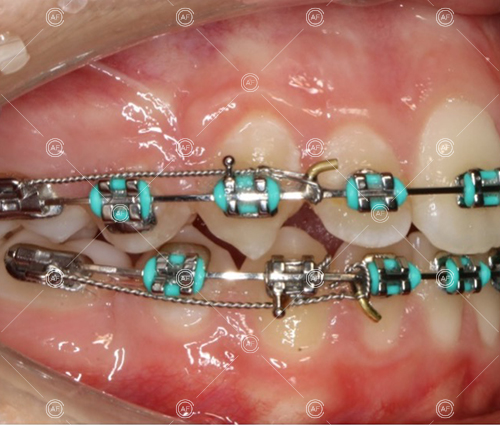

Treatment progressed by starting with thin, flexible nickel titanium archwires of a round diameter, transitioning to a rectangular nickel titanium archwire before eventually working up to a working archwire (1925 stainless steel).

Residual space from the extractions were closed using upper and lower nickel titanium closing coils. Class 2 elastics were used to facilitate space closure in order to gain class 1 buccal segments.